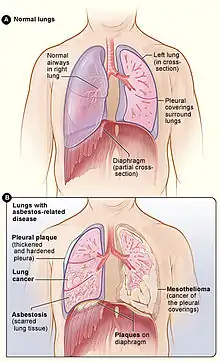

Figure A shows the location of the lungs, airways, pleura, and diaphragm in the body. Figure B shows lungs with asbestos-related diseases, including pleural plaque, lung cancer, asbestosis, plaque on the diaphragm, and mesothelioma.

Figure A shows the location of the lungs, airways, pleura, and diaphragm in the body. Figure B shows lungs with asbestos-related diseases, including pleural plaque, lung cancer, asbestosis, plaque on the diaphragm, and mesothelioma..jpg.webp) Extensive fibrosis of pleura and lung parenchyma